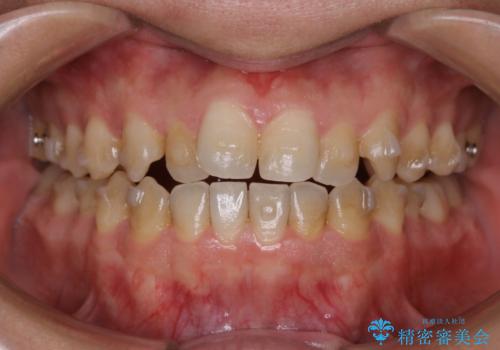

インビザラインで矯正治療中のクリーニング(PMTC)

- 全体的にクリーニングしてほしいとのことで来院されました。

PMTC60分コースを行いました。

インビザラインでの矯正治療は、歯の表面にアタッチメントといって白い突起を付けますので、材料の質的にも普段よりも汚れがかなり付着します。着色も付きやすいです。

虫歯や歯周病が進行しないように定期的にクリーニングすることをおすすめします。インビザライン経過のチェックが2、3ヶ月に1回のためそのくらいのペースで一緒にクリーニング行うことが最適です。